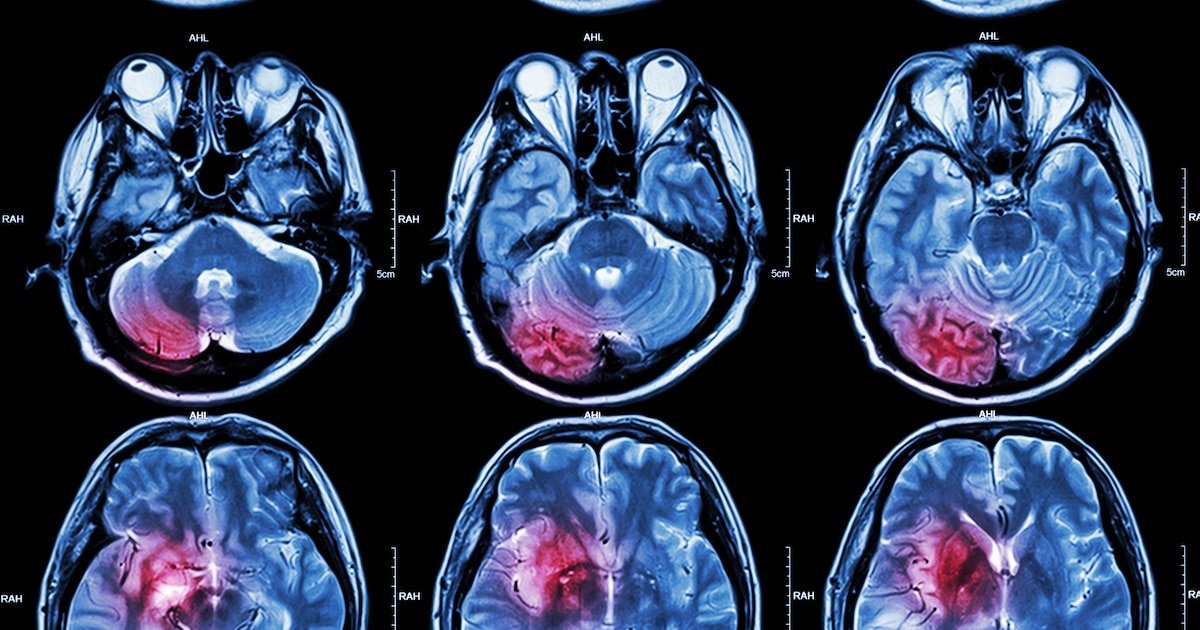

A doença de Parkinson é caracterizada por uma destruição gradual dos neurônios cerebraisum fenômeno que determina o acúmulo e propagação da alfa-sinucleína. Embora se saiba que esta proteína se move de uma célula para outra, até agora não se conhece o mecanismo exato que facilita esse movimento. A equipe liderada por Stephen Strittmatter, professor de Neurologia e chefe do Departamento de Neurociências da Escola de Medicina de Yale, apresentou dados que apontam os transportadores mGluR4 e NPDC1 como atores importantes nesse processo.